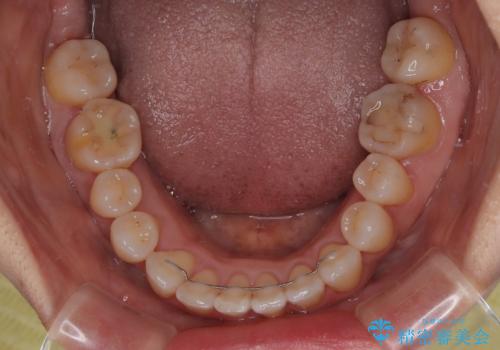

予想通り左側の咬み合わせの調整に苦労をしましたが、最終的には違和感のない咬み合わせを達成することができました。